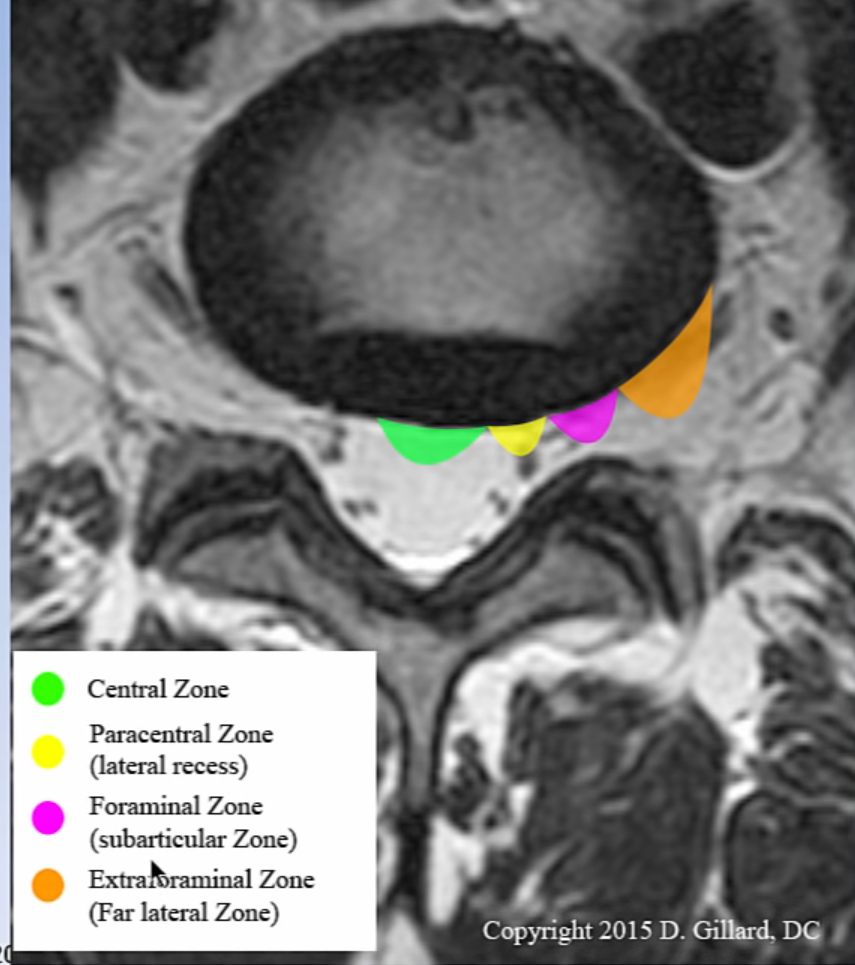

може ли да ми поясните какво представляват тези изменения. Извинете ме , но не съм наясно , а се притеснявам